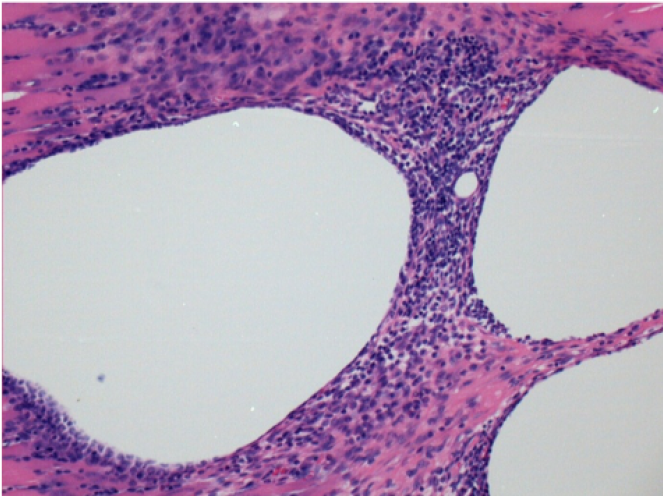

0.5 ml ( 5x 0.1ml) Endopeel SC Injection in the right subcutaneous pretibial area.

R-D10-SC-200X